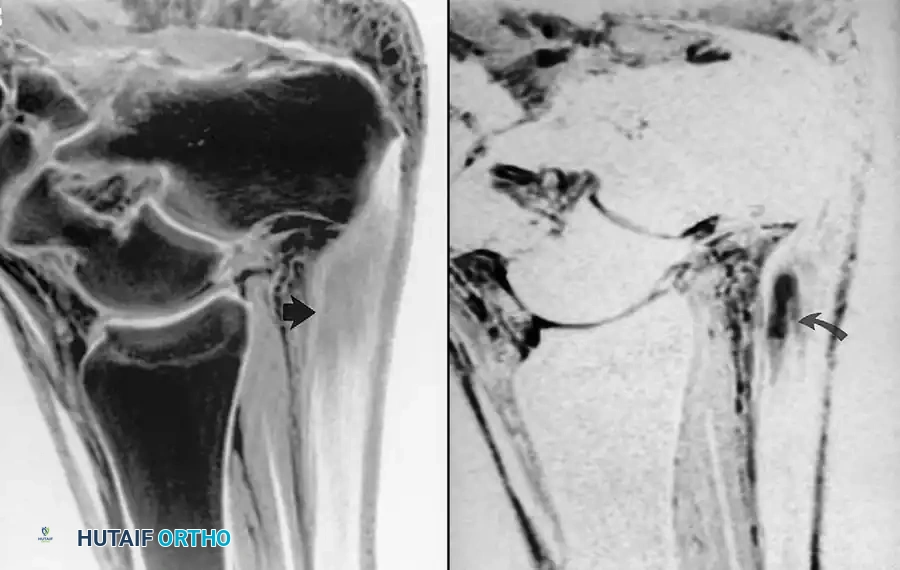

Fig. 2-3 Posterior tibial tendon tear. A, Axial T1-weighted image reveals swollen, ill-defined region of intermediate signal intensity, representing fluid and abnormal tendon. B, Axial fat-suppressed, T2-weighted image shows thickened tendon surrounded by hyperintense fluid.